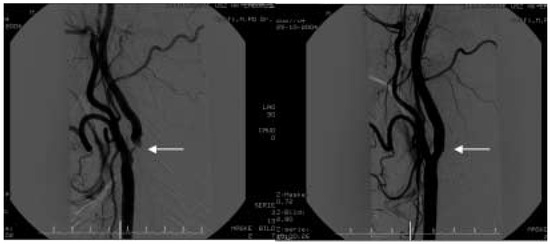

Die Behandlung der Karotisstenose aus der Sicht des Interventionalisten

by Marco Roffi and Franz R. Eberli

Cardiovasc. Med. 2005, 8(9), 306; https://doi.org/10.4414/cvm.2005.01121 - 30 Sep 2005

Viewed by 100

Abstract

In the hand of experienced interventionalists carotid stenting is a valuable alternative to endarterectomy for patients with carotid stenosis. Mechanical emboli-protection systems have been a major advance in the field by reducing the incidence of periprocedural neurologic events. The greatest advantage of carotid [...] Read more.

In the hand of experienced interventionalists carotid stenting is a valuable alternative to endarterectomy for patients with carotid stenosis. Mechanical emboli-protection systems have been a major advance in the field by reducing the incidence of periprocedural neurologic events. The greatest advantage of carotid stenting over endarterectomy is that the outcomes are far less influenced by the comorbidities of the patients. Therefore, the endovascular treatment of carotid disease is particularly suitable for patients at high-risk for surgery. The SAPPHIRE study, which randomised patients at high-risk for surgery to endarterectomy or carotid stenting with filter-emboli protection, demonstrated that patients allocated to carotid stenting had significantly less adverse events. Advantages of carotid stenting over endarterectomy include the reduction of periprocedural myocardial infarctions, the lack of general anesthesia and of neck complications such as cranial nerve lesions. In addition, patients are generally discharged the day following stenting, which leads to a reduction in costs. Patients particularly suitable for carotid stenting are elderly (≥75 years of age), with restenosis following surgery, with stenosis/ occlusion of the contralateral carotid, and those requiring coronary bypass surgery. The only large-scale randomised trial published in non-high risk patients (CAVATAS) showed similar results in patients treated surgically or with balloon angioplasty. The results of ongoing trials should be awaited before expanding the indication of carotid stenting to this patient population off-protocol and in non-specialised centers. Full article

Show Figures

Figure 1